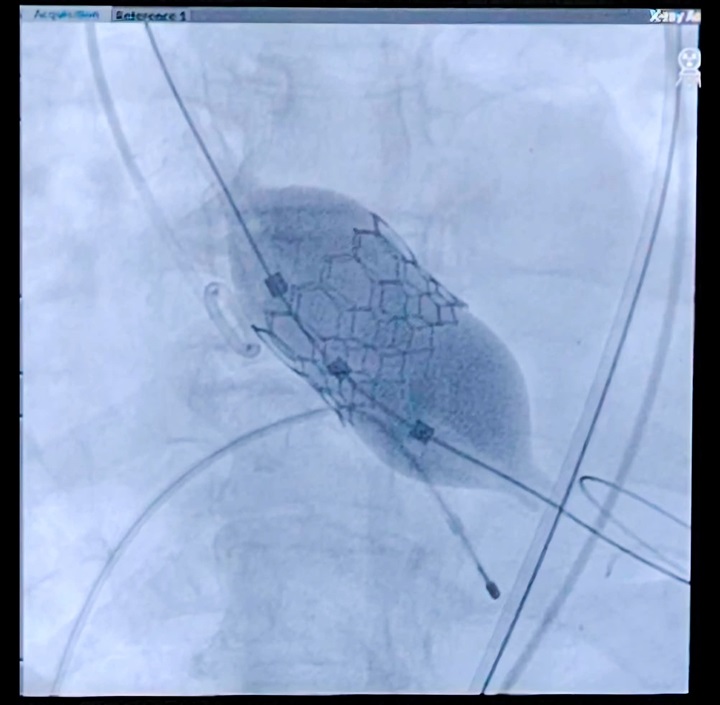

في إطار الدعم المستمر والمتابعة الدائمة لتطوير المنظومة الطبية، وتحت رعاية الأستاذ الدكتور أيمن صلاح رئيس مجلس إدارة مستشفى مصر للطيران، حقق الفريق الطبي بقسم قسطرة القلب إنجازًا طبيًا جديدًا يُضاف إلى سجل النجاحات المتواصلة للمستشفى، وذلك بإجراء زراعة الصمام الأورطي عن طريق القسطرة دون تدخل جراحي أو تخدير عام لمريضة تبلغ من العمر 70 عامًا، كانت تعاني من ضيق شديد بالصمام الأورطي.

وجرى هذا التدخل الطبي الدقيق بنجاح كامل على أيدي فريق طبي متخصص برئاسة الأستاذ الدكتور/ حازم شهاب رئيس قسم القلب، وبحضور الأستاذ الدكتور أحمد السيد يوسف خبير أمراض القلب والصمامات بجامعة عين شمس، في خطوة تعكس المستوى المتقدم الذي وصل إليه قسم قسطرة القلب بالمستشفى، واعتماده على أحدث التقنيات العالمية في علاج أمراض القلب.

وأكد الفريق الطبي أن الإجراء تم في غضون ساعة واحدة فقط، دون الحاجة إلى تدخل جراحي مفتوح أو تخدير كلي، وهو ما أسهم في تقليل المخاطر الطبية وسرعة تعافي المريضة. وقد تم نقلها إلى غرفتها عقب الانتهاء من العملية مباشرة، وهي في حالة صحية مستقرة وجيدة، وسط متابعة طبية دقيقة.